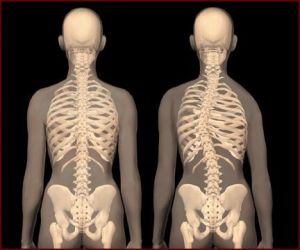

肩和骨盆的傾斜,長期不對稱姿勢,優勢手、下肢不等長,肌肉凹側組織緊張,凸側組織薄弱、被牽拉。

(1)側凸:即部分脊柱棘突偏離身體中線稱脊柱側彎,有左側凸、、右側凸及S形彎,C形彎。

(2)後凸:指胸段脊柱後凸超過生理曲線範圍者。脊柱側凸